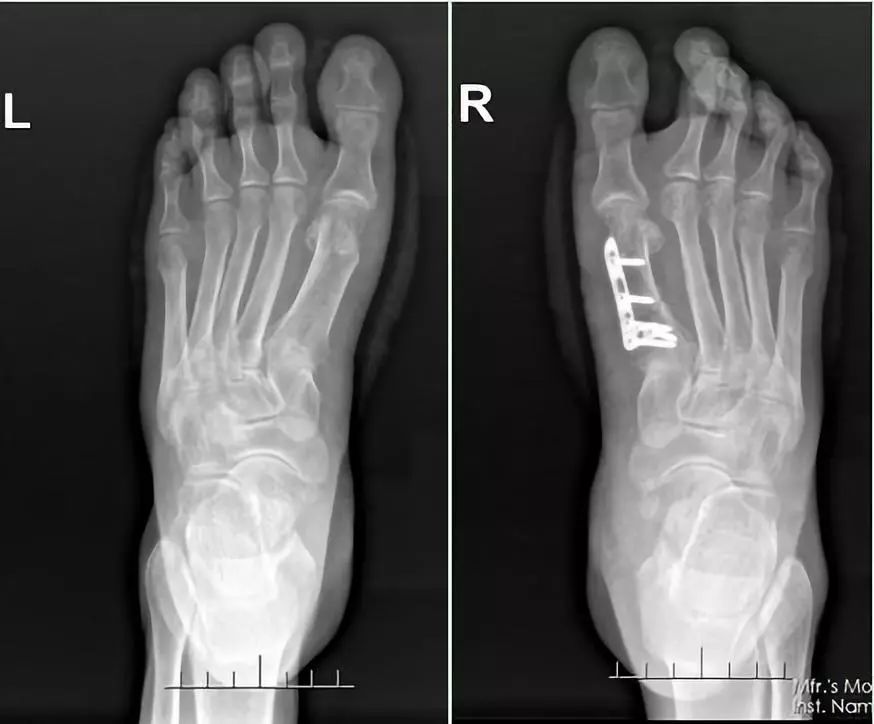

柴亚胜接诊时发现,患者左脚大拇指往其他趾头的方向弯了近30°,而右脚就更加严重了,外翻角度将近40°,严重挤压了第二趾和第三趾。柴亚胜说,这是非常典型的“踇外翻畸形”,大多数人发病的原因跟常年穿高跟鞋、尖头鞋有重要关系。不过像李兰这样的情况就比较严重了,需进行截骨矫形手术才能恢复正常走路。

跟家人商量后,李兰决定接受手术治疗。完善相关检查后,柴亚胜为患者实施了“左脚第一跖骨头截骨、踇外翻矫形术和右脚第一跖骨截骨矫形内固定、踇外翻矫形术”。术中,患者左右脚的踇外翻得到有效的纠正。术后疼痛的症状明显减轻,术后一周便可以穿减压鞋下床走路了。